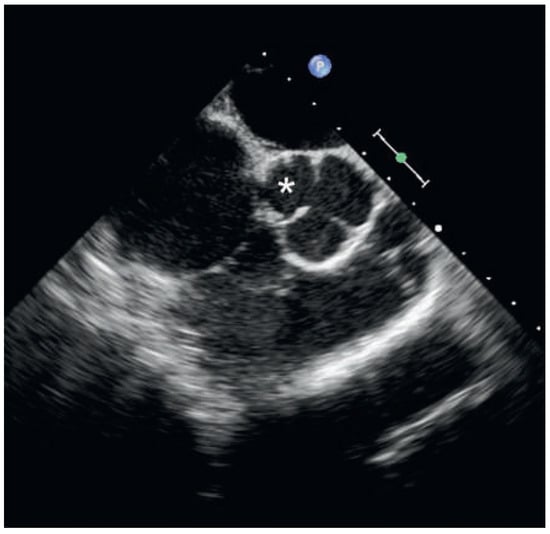

Case report